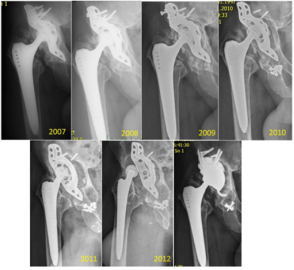

In our institution, 549 hips were re-implanted in the 4-year period from 2003 to 2007, with 243 of those re-implantations involving an acetabular component. BS plate was used in 78 (28.8%) of those latter cases, with only 8 of the patients being lost to follow-up. Also, in our institution, since 2000, we have preferred to perform non-cemented total hip replacements (THRs) in younger patients (under 70 years-old), and we have noted the need to perform re-implantation for subsequent defects, which tend to be larger, and especially so with the acetabular component (Figure 4). All patients with BS plate re-implantation were assessed by x-ray of the pelvis to identify cases of asymptomatic loosening; only 5 cases (7%) were found. In follow-up, the patients were re-operated (two times in total for 4.2% of the cases to address complete loosening or for an infectious complication in 2 cases (2.8%), with one needing full extraction of the BS plate. (Figure 5) provides an excellent representation of a case of the BS plate loosening itself.

Figure 5: Representative case of mechanical loosening of the BS plate. The proximal screws were fixed into defective bone, and a final revision was made by implantation of a hemispheric acetabular modulus. The final panel shows the results of the re-reimplantation (occurred and imaged in 2012).

The migration occurred proximally, with breakage of the proximal screws and migration of the plate (from 2009). Then, a mixture of the screws is seen in the bottom of the joint space (2010) and luxation (2012). In the same year (2012), we re-admitted the patient for re-reimplantation and implanted a hemispheric modulus with excenter and larger revision stem. In Figure 6, a case of mechanical loosening of the BS plate is presented. This event does not, generally, lead to positional plate loosening. Instead, the plate protrudes into the pelvis slightly, though it is still capable of full-weight bearing.